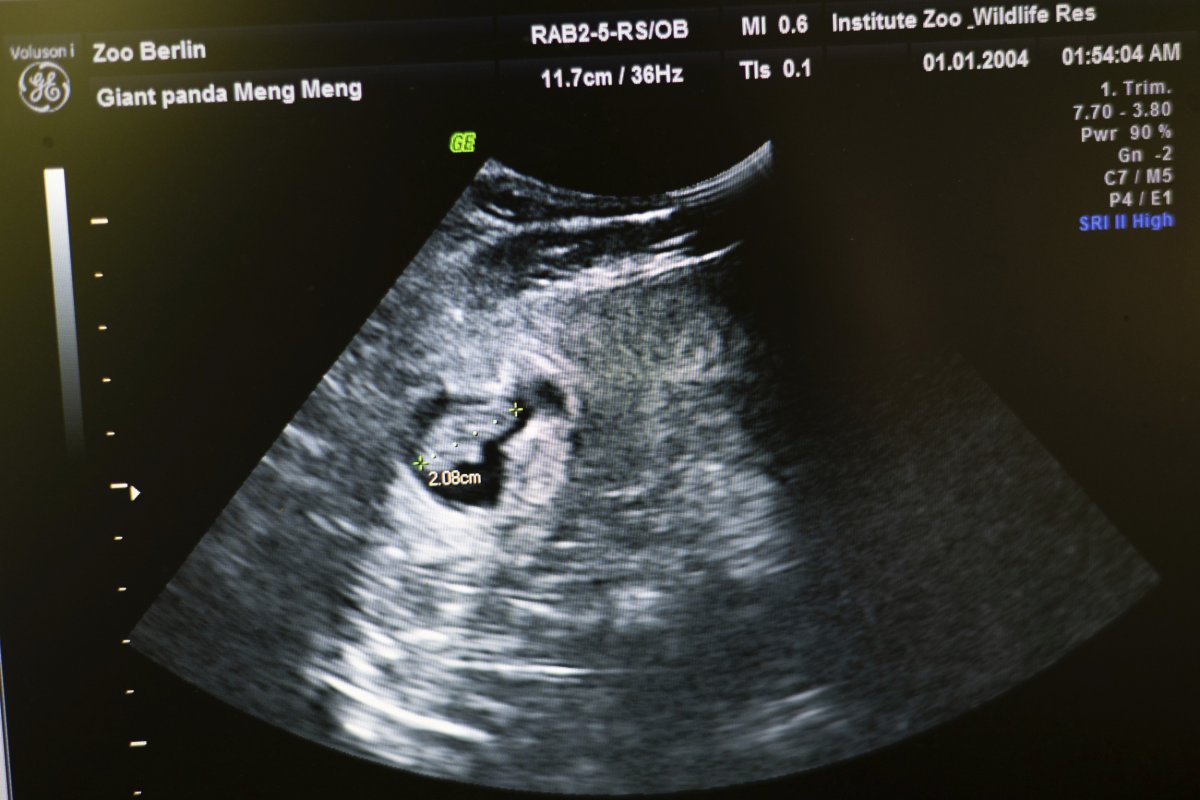

Meng Meng, who is mom to 5-year-olds, Pit and Paule, surprised everyone 11 days ago, when an ultrasound confirmed she was pregnant.

The newborns, whose sex has not yet been determined and are so far unnamed, weighed in at a mere 6 ounces and 4.8 ounces, and measured just 5 and a half inches in length.